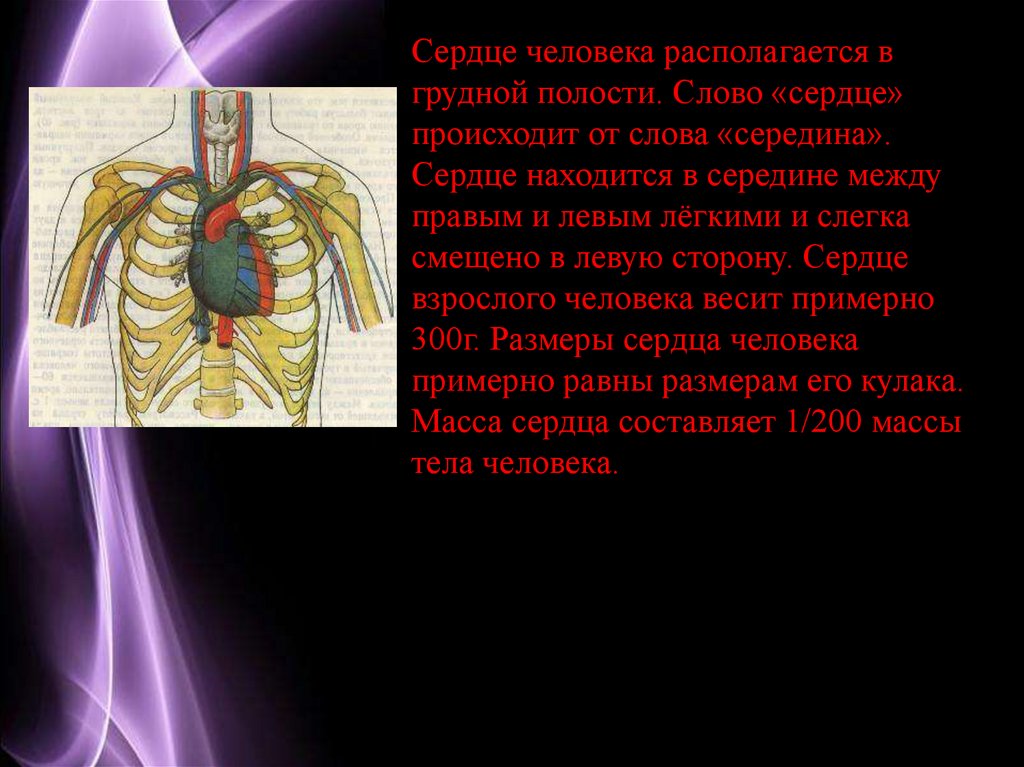

Сердце у человека располагается в грудной полости.

Расположение сердца у человека.

Анатомическое расположение сердца.